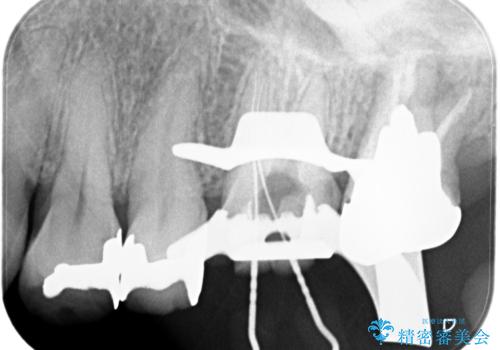

【再根管治療】オールセラミッククラウンによる修復

- 治療途中の歯があることを主訴に来院されました。

根管治療を行なったのちオールセラミックにて修復治療を行なっております。

第二大臼歯の治療は希望されませんでした。